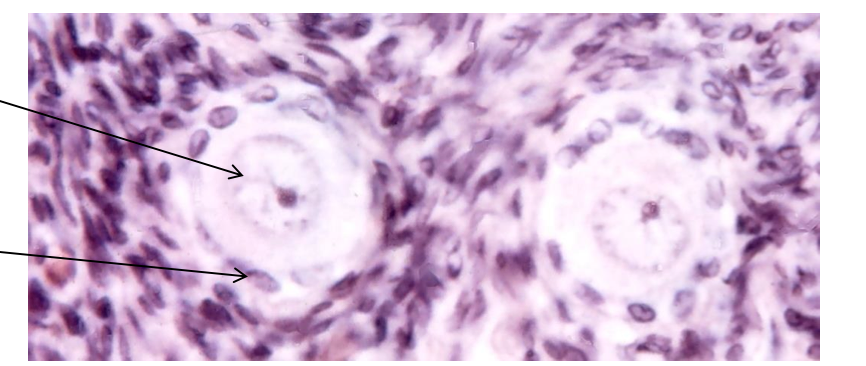

primoridal follicle

preantral follicle